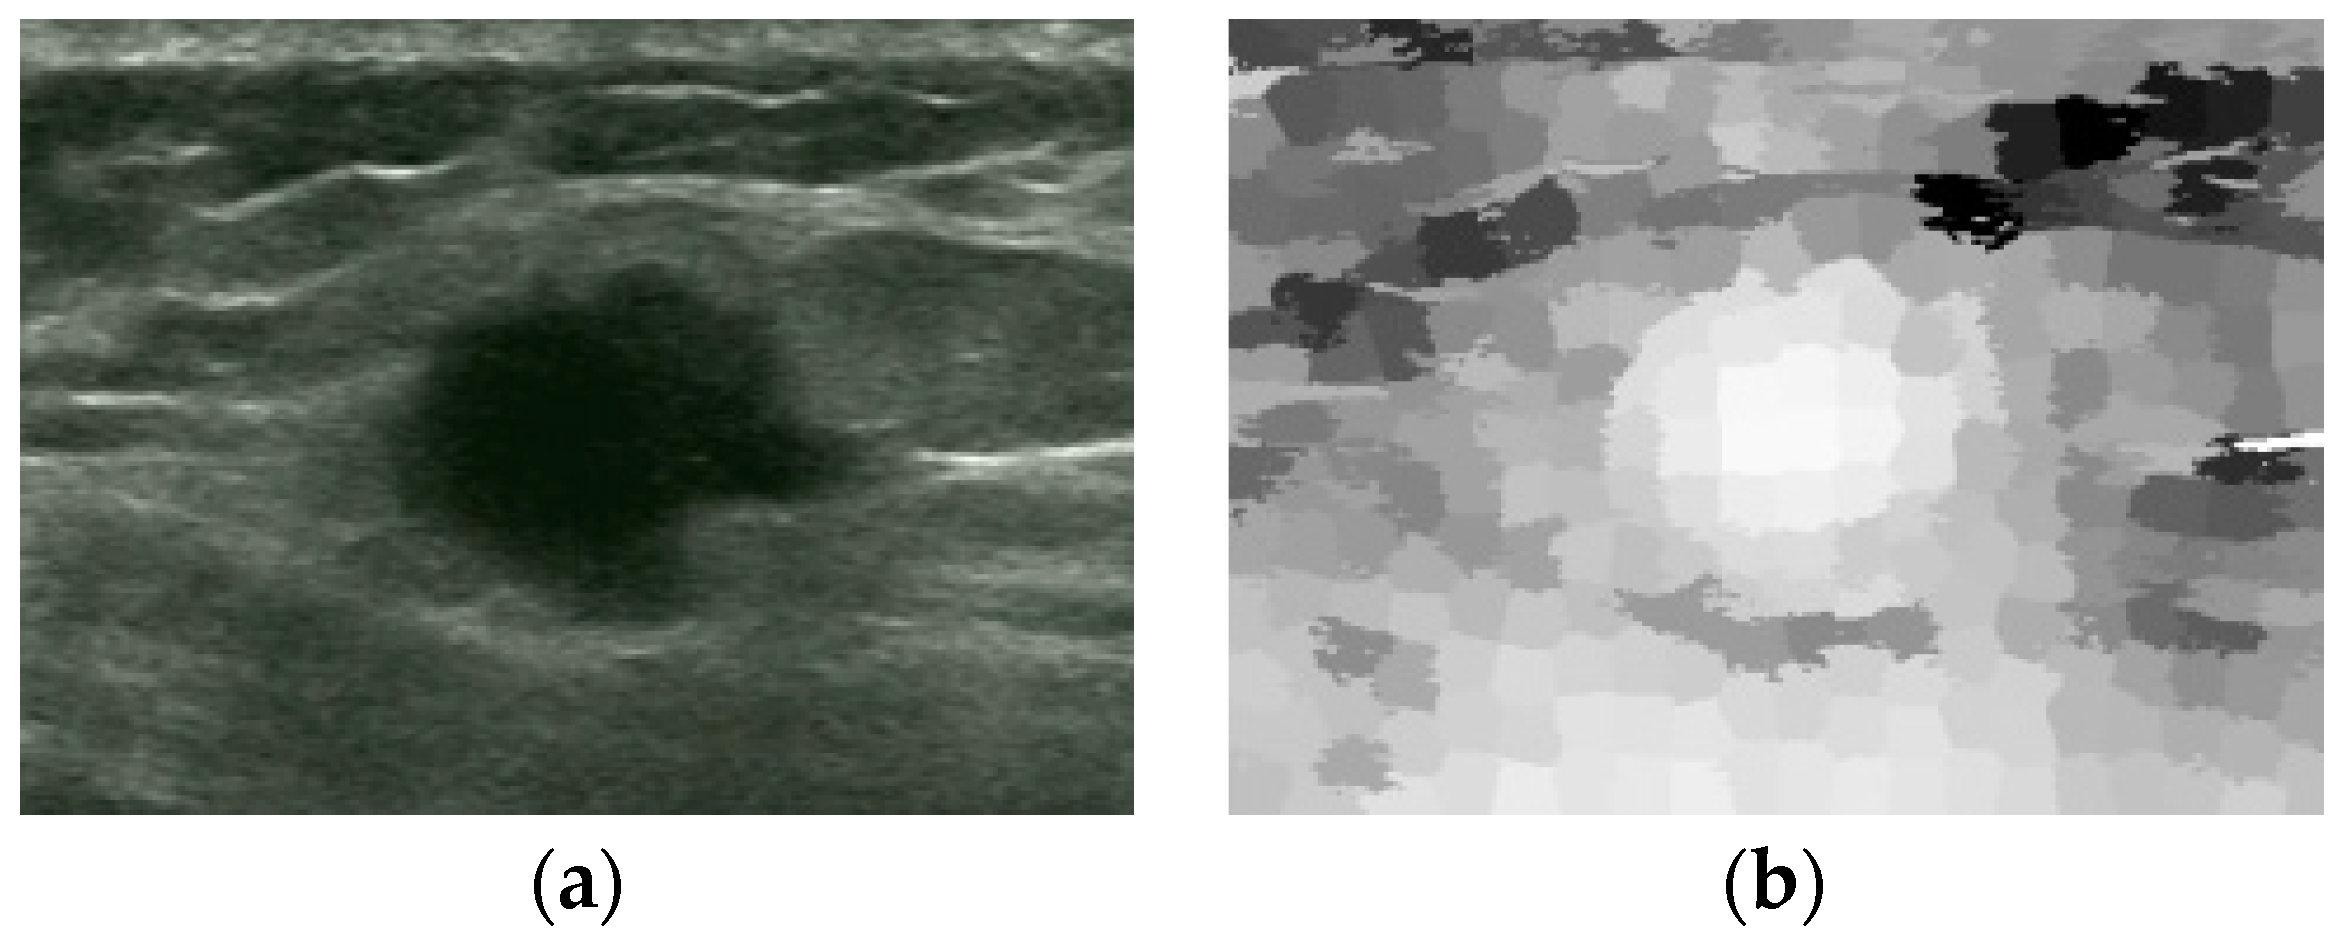

An Automatic Localization Algorithm for Ultrasound Breast Tumors Based on Human Visual Mechanism

Xie, Y.; Chen, K.; Lin, J. An Automatic Localization Algorithm for Ultrasound Breast Tumors Based on Human Visual Mechanism. Sensors 2017, 17, 1101. https://doi.org/10.3390/s17051101